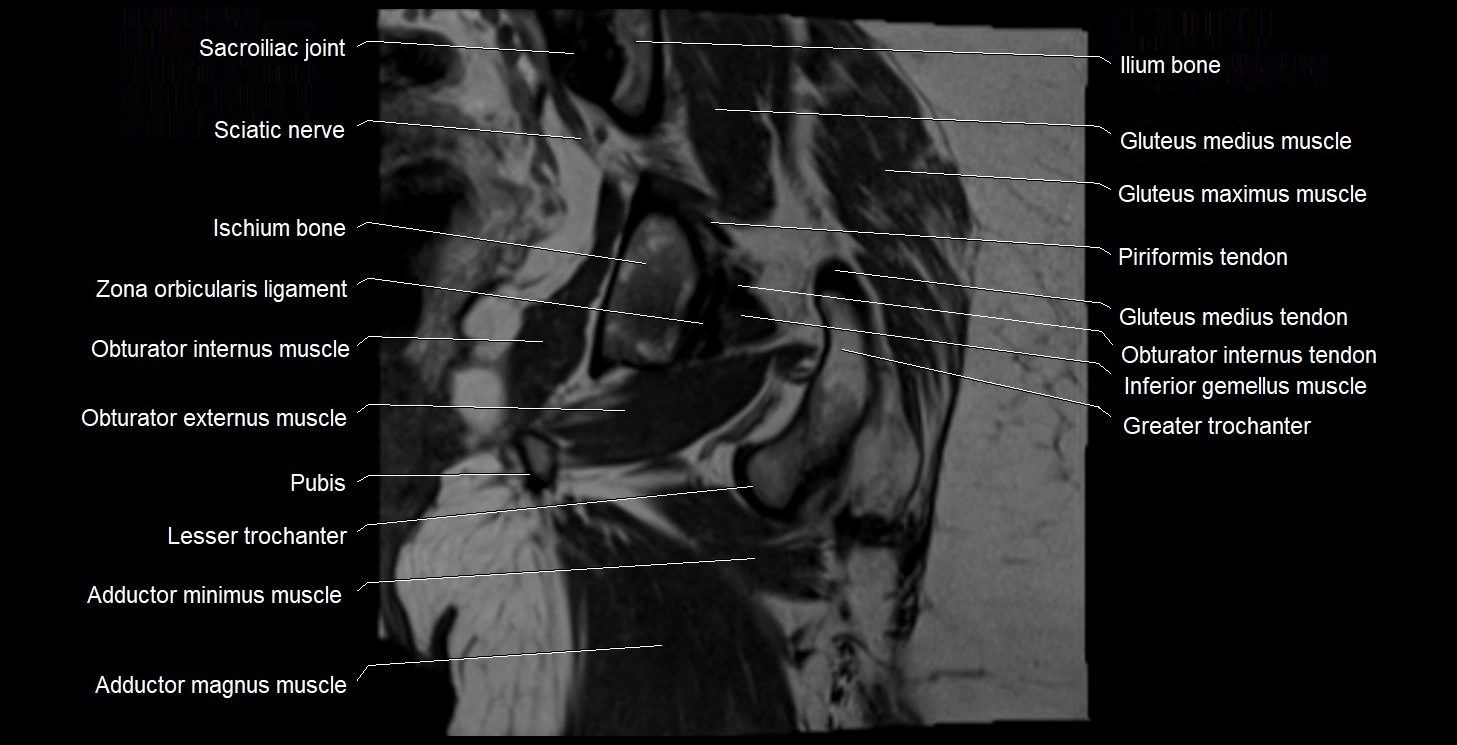

- Adductor minimus muscle

- Greater trochanter

- Ilium bone

- Inferior gemellus muscle

- Ischium bone

- Lesser trochanter

- Lumbosacral trunk

- Obturator externus muscle

- Obturator internus muscle

- Obturator internus tendon

- Sacroiliac joint